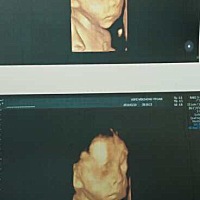

宝宝2个月20天

两个多月的我甜心,记录一下。